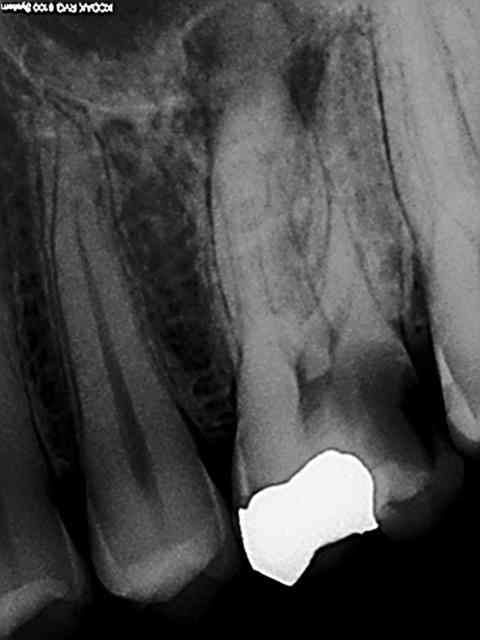

Radio cone en place avant obturation, j'ai rarement un problème avec le mv2 avec lequel soit je n'arrive pas à l'apex soit je bute sur la paroi du mv1 si ceux ci sont en y. Jamais de cathétérisme manuel seulement une localisation d'apex au S1 protaper sur endomaster, repère visuel sur les graduations puis r25. récapitulation en plusieurs fois si les instruments forcent toutefois. Je vais essayer la localisation au gold pour voir si ca dit la meme chose que l'endo master. Ci dessous l'endo molaire du jour c'est tout frais (en général je poste les endos de la journée) ici en l'occurrence patient vu pour la premiere fois, status radio + endo 45 mn.

La pèche a été bonne sur le status endo sur 45 à suivre.))))))

Superbe endo !! Tu ne reconstitues pas en systématique tes dents avant endo ( cavité distale sur RX)?Tu ne fais donc jamais de radio lime en place avant préparation des canaux? Ta longueur de preparation est-elle toujours correcte? Jamais de faux positifs? Tu utilises la localisation uniquement avec l'endomaster et non le reciproc?

Ca c'est cones en place))))), la cavité distale ne m'a pas dérangée dans ce cas (digue bien plaquée en distal et étanche) , sinon oui je fais une reconstitution pré endo si il y a des fuites.

Jamais de limes en place (j'en ai pas) localisation au s1 sur endo master uniquement puis éventuellement avec un mtwo 25 à la fin pour être sur d'être à l'apex en 25 -06 (une formalité).